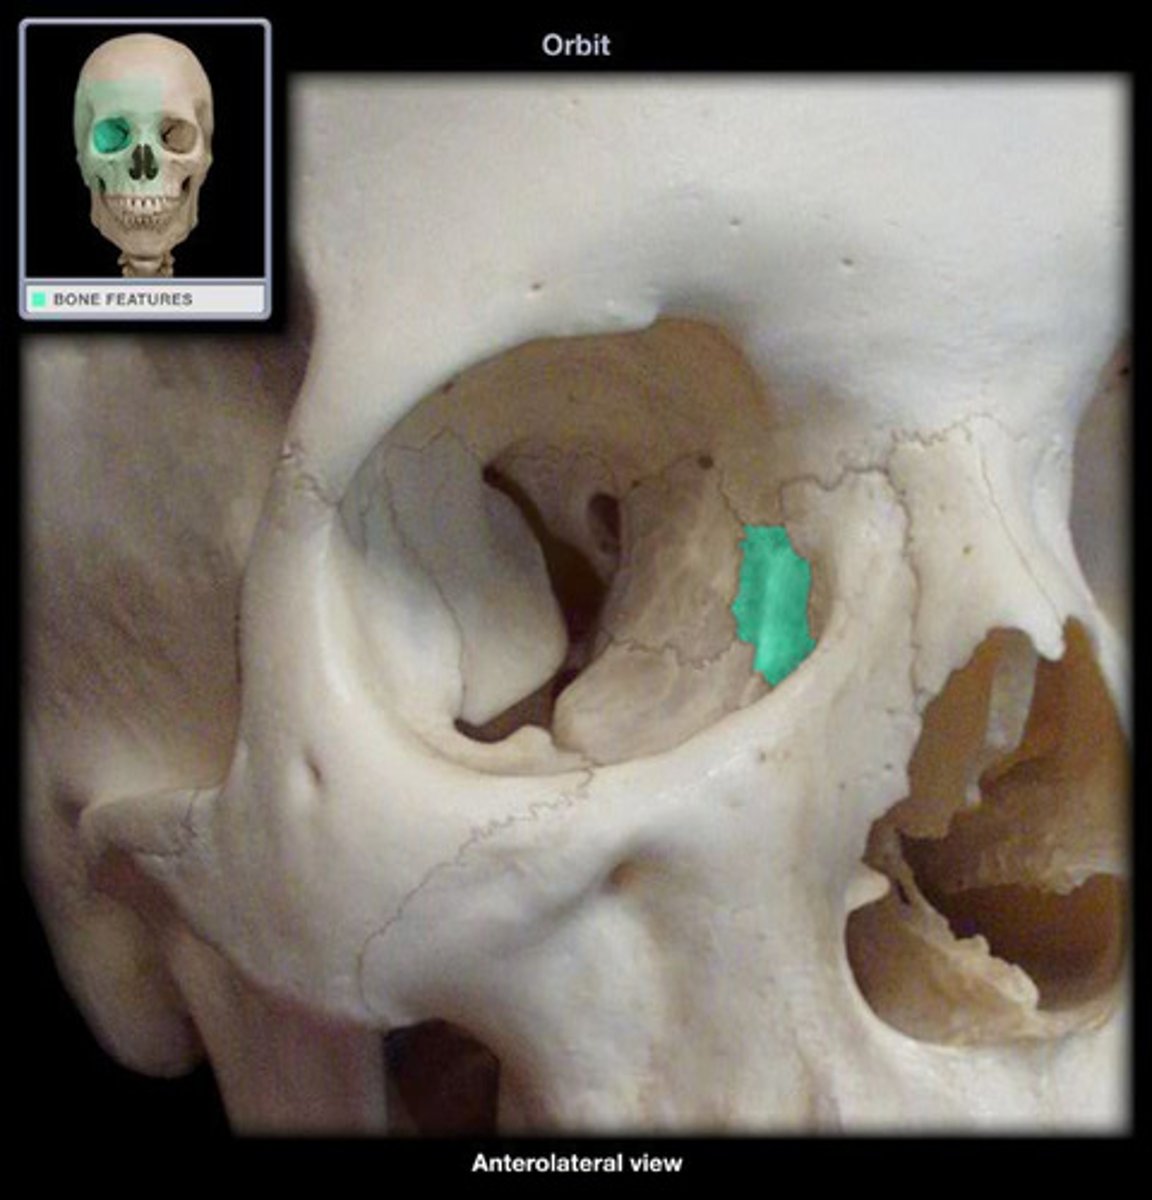

Lacrimal Bone

Optic foramen